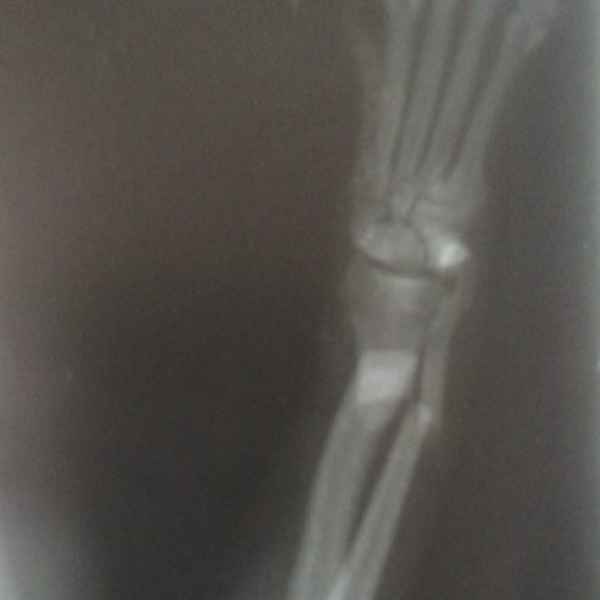

Вот что значит неудачно спрыгнуть с дивана. Это рентгеновские снимки одного из наших пациентов. Сначала хозяева обратили внимание на хромоту, а потом поняли, что у питомца очень болит лапа. Ещё бы не болело - поперечный перелом костей предплечья. Операция, установка DCP-пластины, восстановление, и он снова активный и жизнерадостный.

Этот пациент поступил к нам с кусаной раной левой грудной конечности После рентгенологического исследования обнаружили перелом костей предплечья. Сложность операции заключалось в том, что дистальный отросток лучевой кости был очень коротким. Хирургом нашей клиники было принято решение установить блокируемую lcp пластину. В данный момент пациент полностью восстановился..